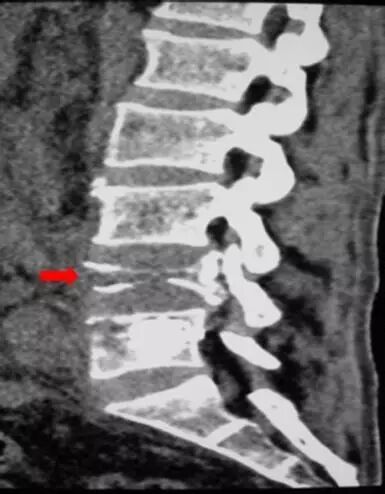

老张是一例左肾癌切除术后1年半的患者,近段时间,老张总觉得腰部酸痛不适,遂进行了腰部CT检查,发现腰3、4椎体转移,病灶呈溶骨性破坏(箭头所示),随后老张接受了腰3、4椎体放疗,并辅以双磷酸盐药物治疗,疼痛获得缓解,老张对治疗效果很满意,然后进入了随访阶段。